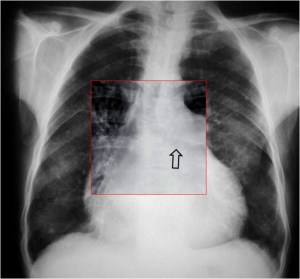

SIGNO DE LA ALTERACIÓN DEL CONTORNO AÓRTICO

La irregularidad, abombamiento o borramiento del arco aórtico en la radiografía de tórax en bipedestación o en decúbito supino, en un paciente con traumatismo torácico, obliga a descartar rotura aórtica como causa de dicha alteración. La flecha muestra el contorno aórtico anómalo. Además, hay un aumento de densidad en el hemitórax izquierdo correspondiente a derrame pleural –hemotórax en este caso-, que refuerza la sospecha de rotura aórtica.